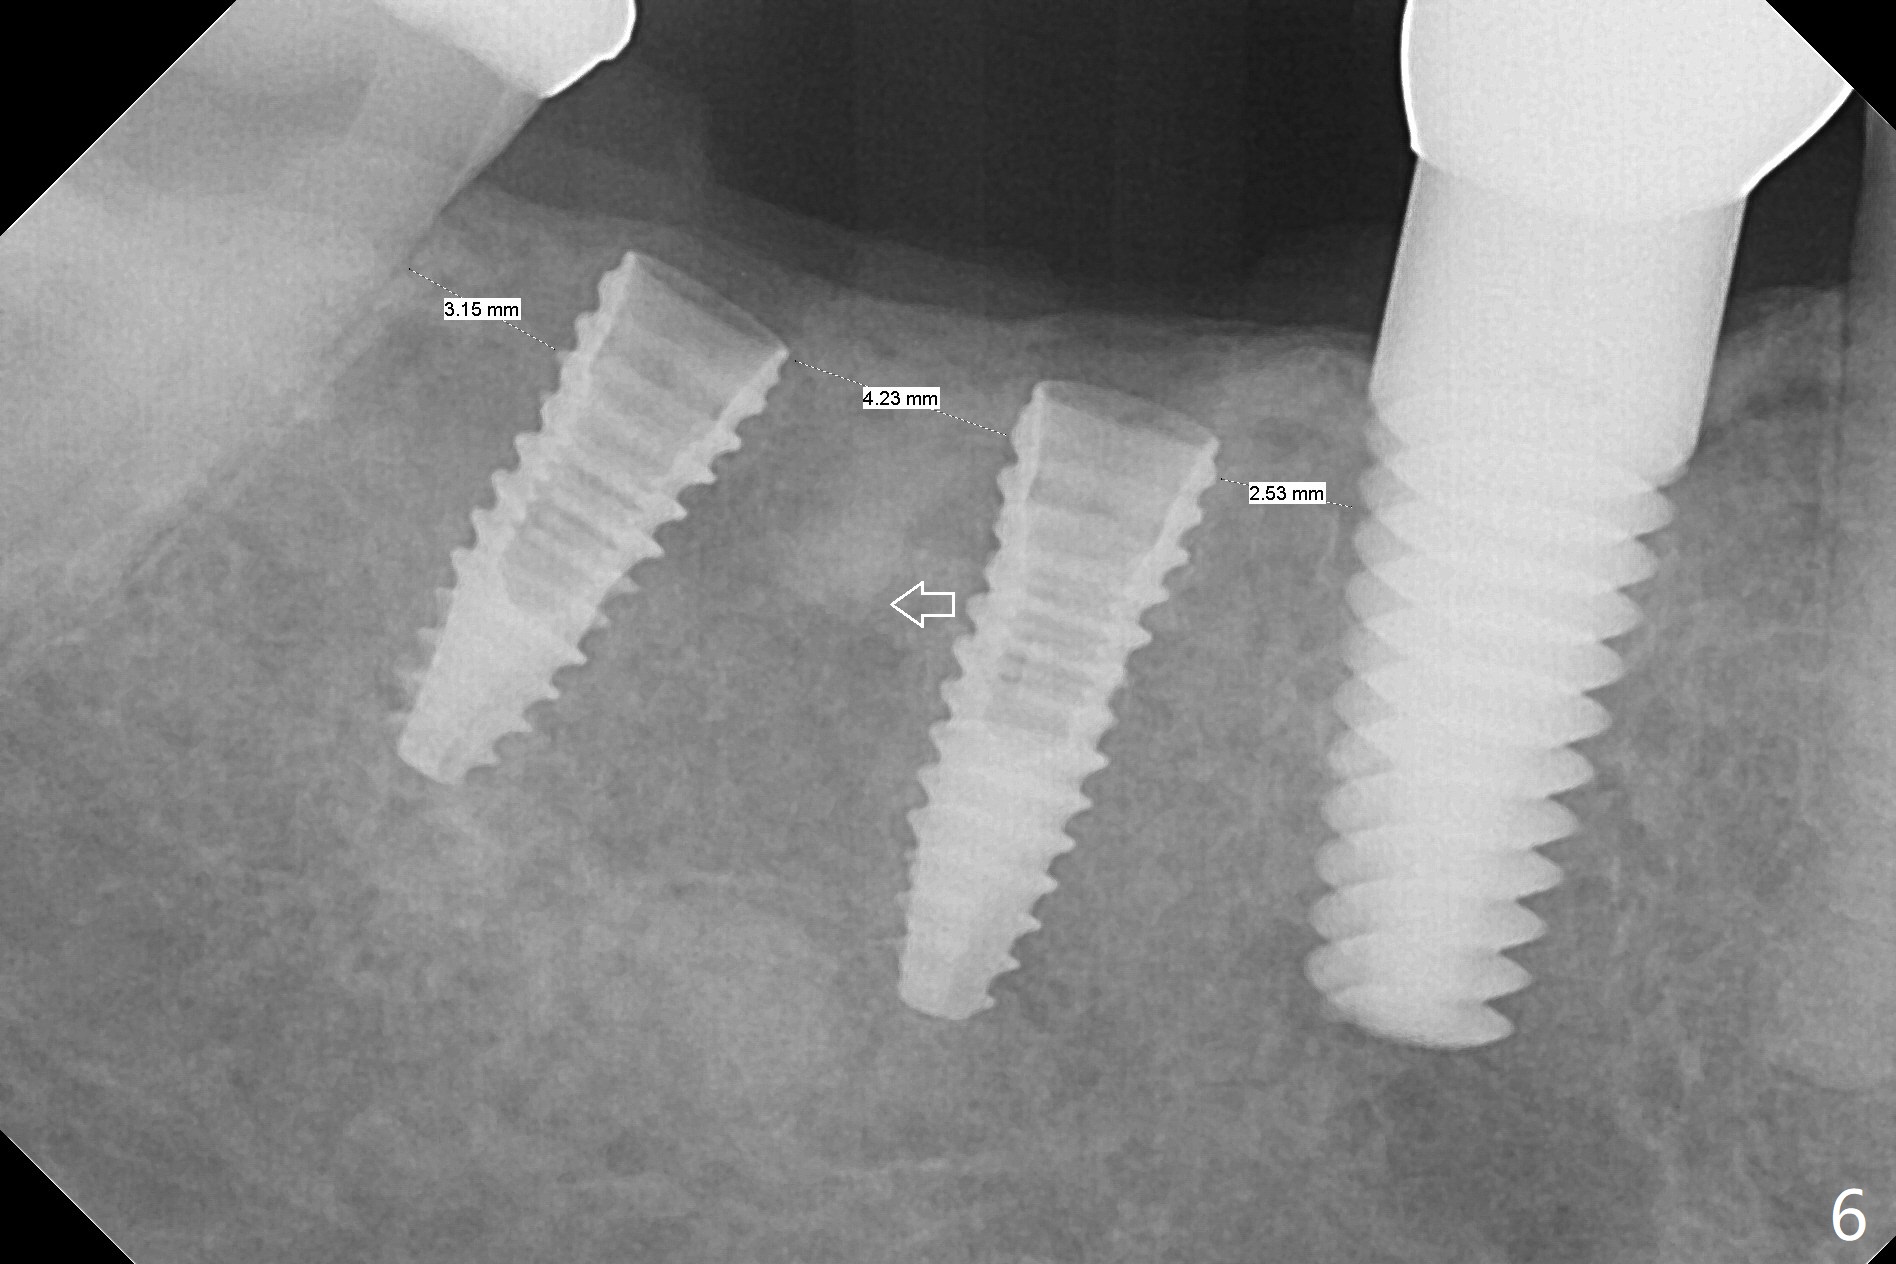

In fact, detailed measurements after parallel pins indicate that the osteotomy at #30 should be moved distal (Fig.5 arrow), which is consistent with post placement measurements (Fig.6).